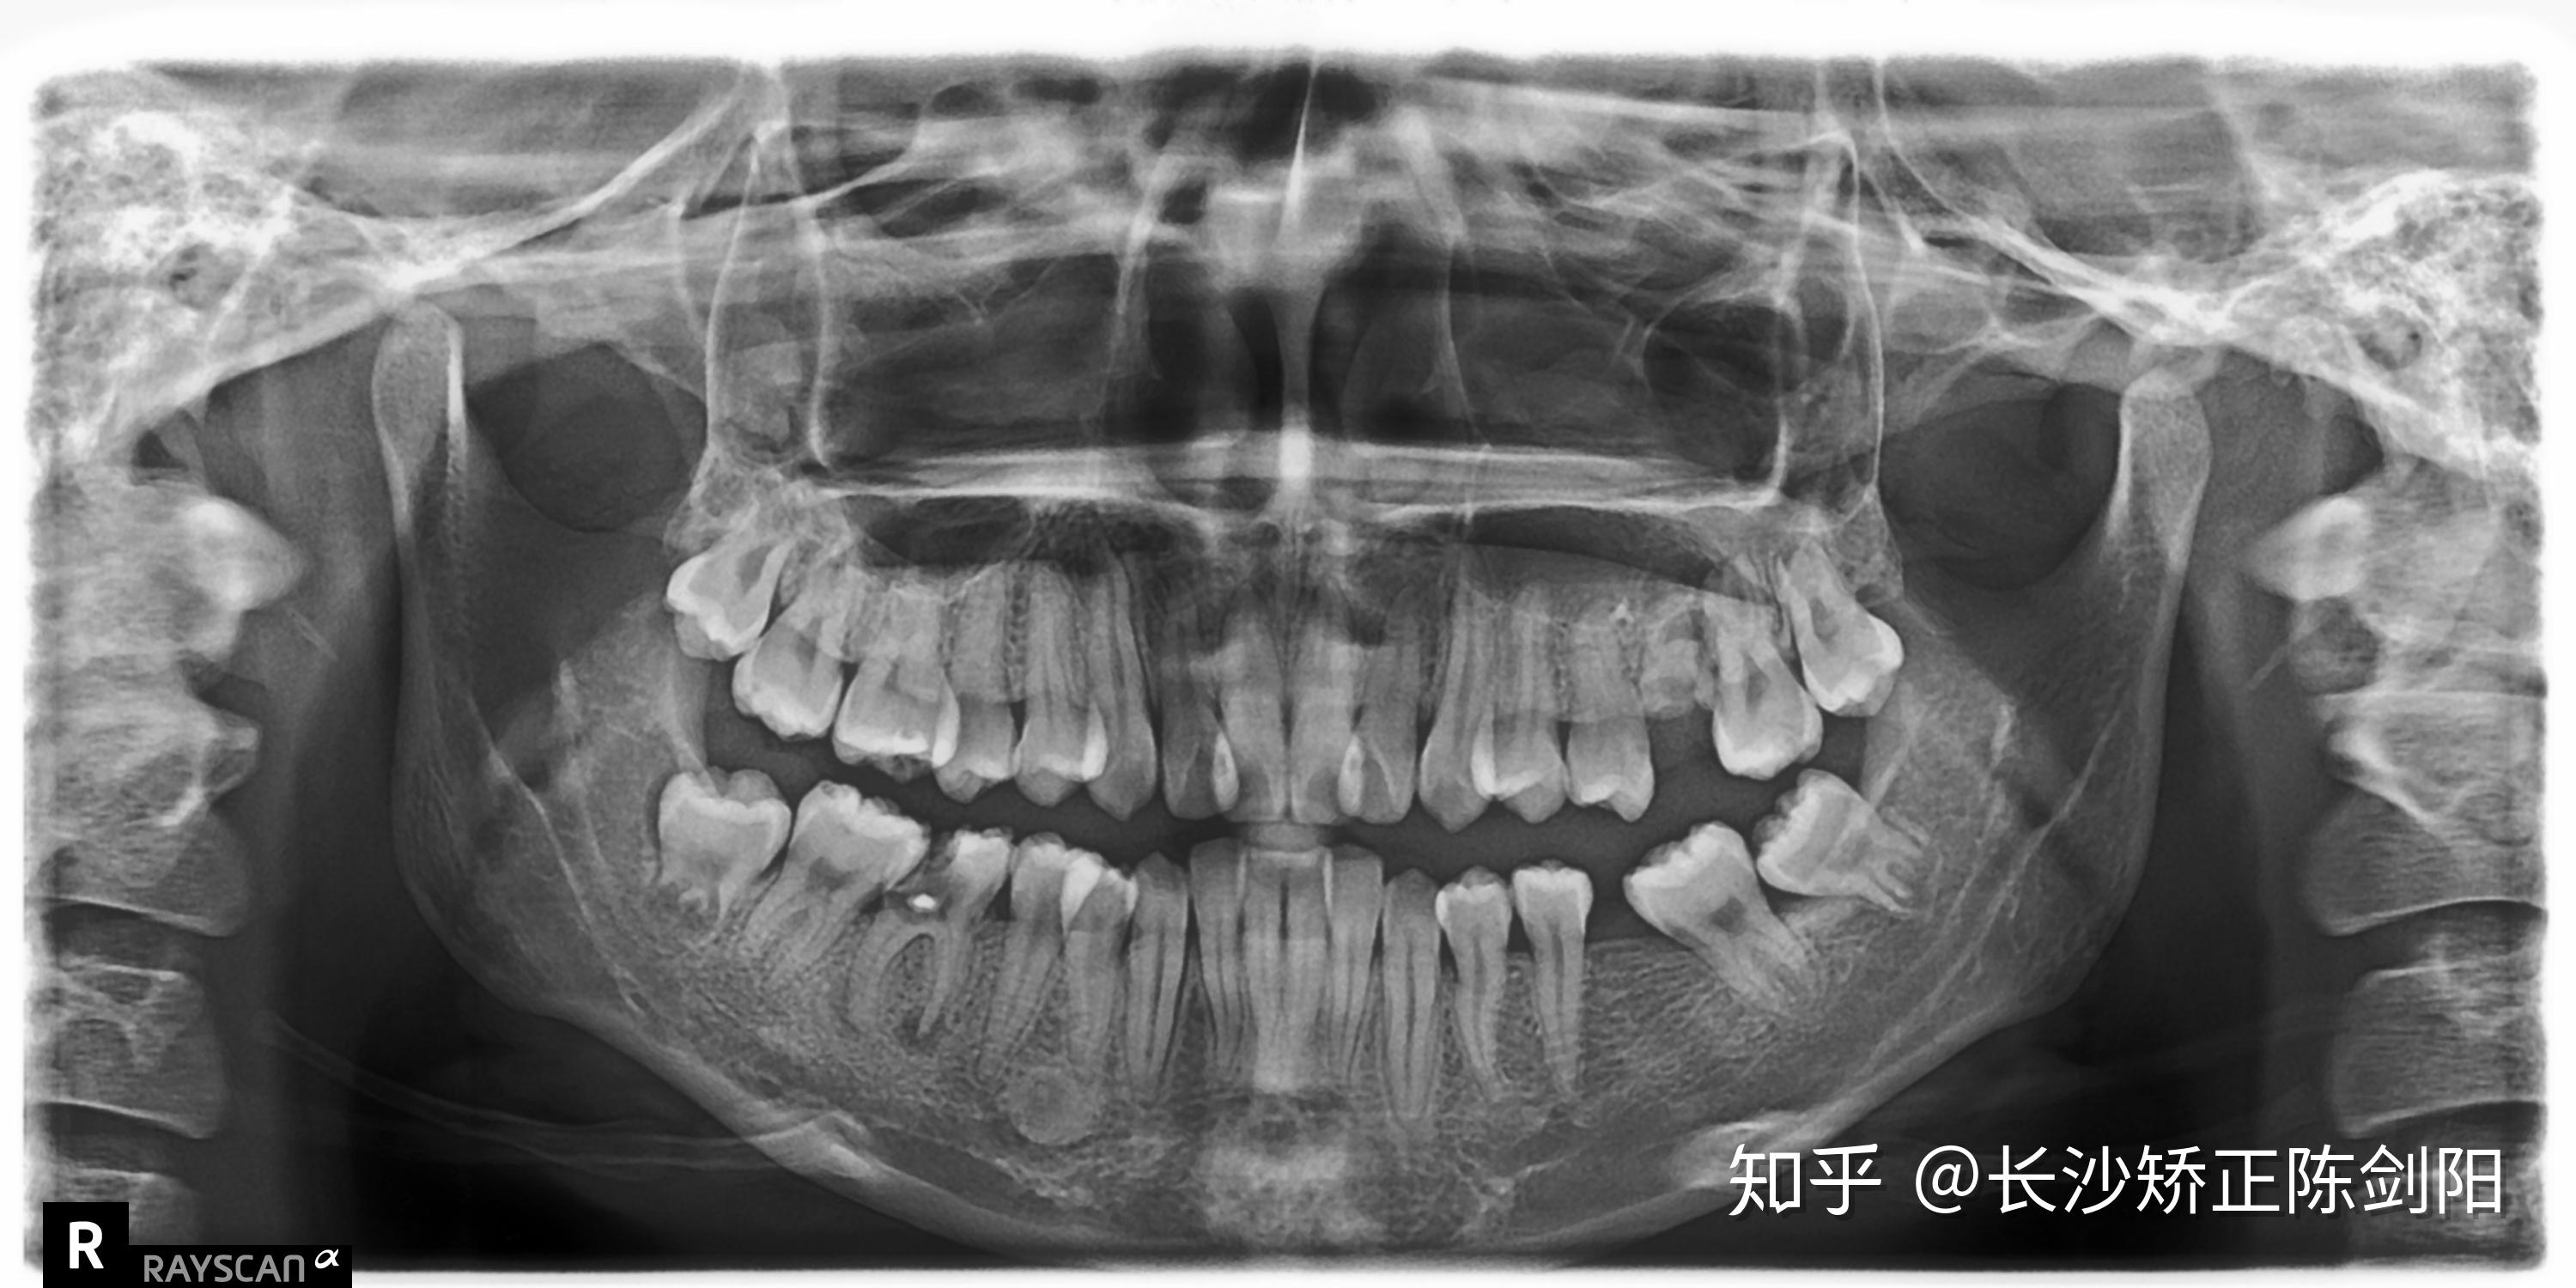

长沙牙齿矫正有蛀牙可以矫正牙齿吗

图片尺寸3000x1500